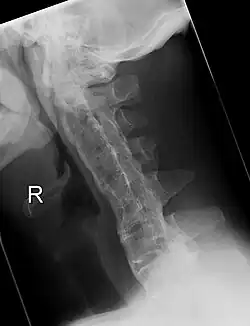

Lateral X-ray of the neck in ankylosing spondylitis -

Cervical spine showing ankylosis (fusion) -